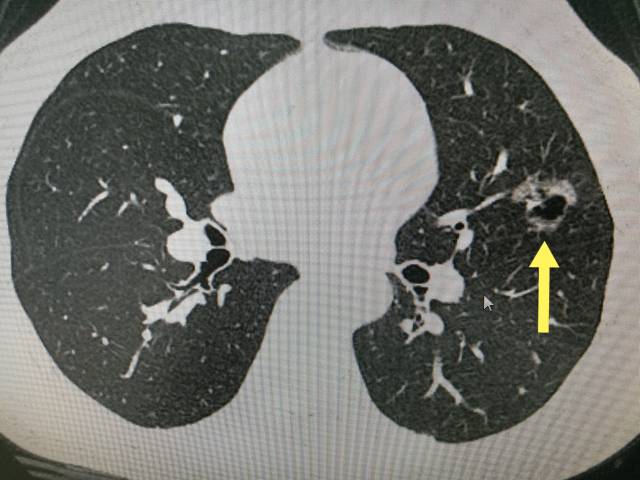

33岁女性磨玻璃结节2年伴空泡征血管征,但只有6毫米,要不要手术_原位